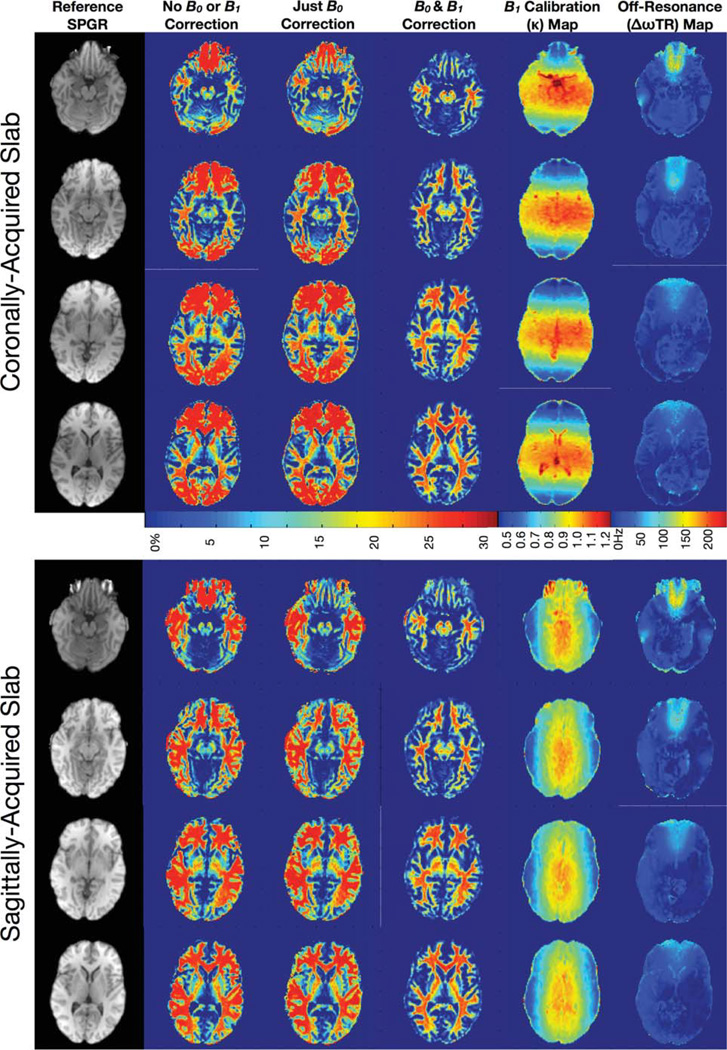

FIG. 1.

Example illustrations of the affects of B0 and B1 inhomogeneity on mcDESPOT derived myelin volume fraction maps.

Representative imaging results are shown in Figures 9– 12. Figure 9 contains comparative sagittal and coronally acquired myelin water volume fraction’s maps, reformatted as axial slices at approximately the same level, calculated without B0 and B1 correction; with only B0 correction; and with both B0 and B1 correction. These data clearly demonstrate the influence of flip angle and off-resonance errors in the derived maps. Errors related to flip angle inhomogeneity are greatest along the slab-select direction at the edges of excited volume and correspond to the profile of the RF pulse. Errors resulting from off-resonance conditions are maximal near the sinuses, inner ear, and brain stems.

FIG. 9.

Representative axially reformatted slices through the myelin water fraction map volumes calculated without any correction; with only B0 correction; and with B0 and B1 correction, along with the corresponding calculated B0 map and B1 calibration map and an example reference T1-weighted SPGR image.

Figure 10 displays maps of each of the six mcDESPOT parameters (T1,M, T1,F, T2,M, T2,F, fM, and τM) calculated without B0 or B1 correction; with only B0 correction; and with both B0 and B1 correction. As observed in Fig. 8, these data exemplify the B0 and B1-related errors in each of the multicomponent parameters and demonstrate the corrective ability of the presented flip angle and off-resonance modeling techniques. In general, it is noted that flip angle errors appear to predominately affect the T1 measures, whereas off-resonance principally influence the T2 measures. However, both have significant influence on the derived myelin water fraction estimates.

FIG. 10.

Axially reformatted through each of the mcDESPOT parameter maps calculated without any correction; with only B0 correction; and with B0 and B1 correction. As shown in the simulations, both B0 and B1 inhomogeneity result in widespread error in each of the multicomponent parameters. These areas of artifact are significantly improved in the corrected images.

In Fig. 11, we show axially reformatted images through the uncorrected; B0 only; and fully B0 and B1 corrected myelin water volume fractions maps at different levels throughout the brain. Again, these images demonstrate not only the severity of artifact in the uncorrected maps but also their effective removal and elimination when B0 and B1 are modeled and appropriately accounted for.

FIG. 11.

Example axially reformatted T1-weighted SPGR, calculated myelin water fraction, B0 and B1 calibration maps from a single volunteer’s data at different levels through the brain volume. [Color figure can be viewed in the online issue, which is available at wileyonlinelibrary.com.]

As noted throughout the numerical simulations, areas of off-resonance translate into over-estimations of myelin water fraction. Similarly, incorrect knowledge of the transmitted flip angle, such as at the edges of the excited volume, also translate into myelin water fraction over-estimation. A comparison of mean myelin water fraction values obtained from frontal white matter is shown in Table 1 and supports the qualitative results observed in Figs. 8–11. Averaging the corrected results from both orientation acquisitions across all four volunteers, mean frontal region white matter values were: T1,M = 387 ± 26 msec, T1,F = 946 ± 53 msec, T2,M = 10.4 ± 3.2 msec, T2,F = 108 ± 12 msec, fM = 0.232 ± 0.0017, and τM = 98 ± 26 msec. No significant difference was noted between the values derived from the sagittal or coronally acquired data. These values compare favorably with previously reported values at 1.5 T of T1,M = 350–460 msec, T1,F = 970 msec, T2,M = 10–55 msec, T2,F = > 55 msec, and fM = 0.12–0.32, respectively (12,13).